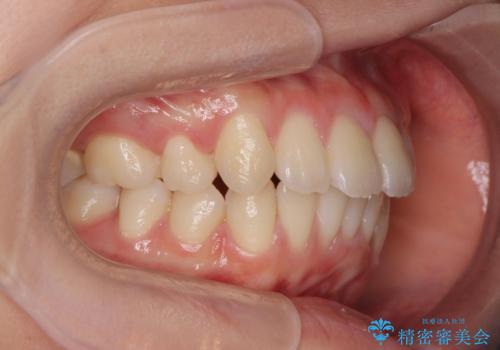

突き出た前歯の改善!マウスピースで再矯正

- 5年前にワイヤー矯正治療を終了したが、突き出たように見える前歯の仕上がりが気に入らず、再矯正治療を希望され来院されました。

マイクロインプラントを用いた遠心移動とIPRを行うことによる前歯の突出感の改善をマウスピース矯正治療で計画します。

突出していた前歯の角度が大きく改善し、審美的な仕上がりに満足いただくことができました。